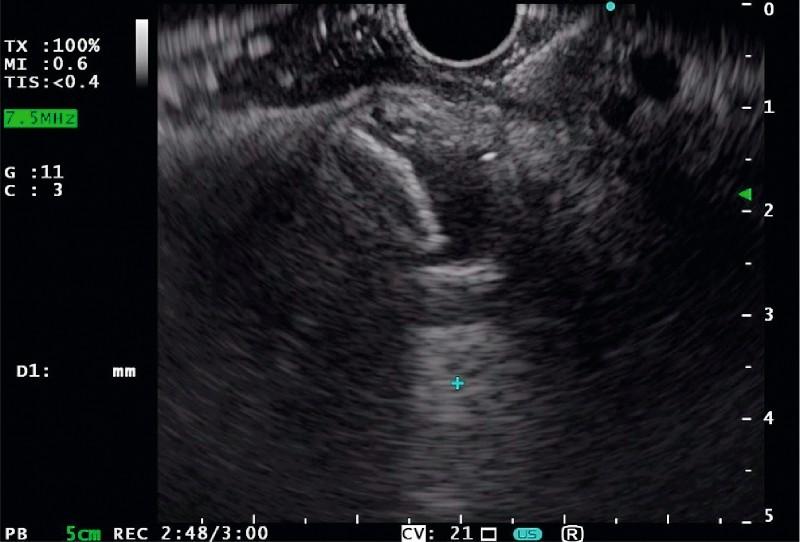

Recently, a novel lumen-apposing fully covered self-expanding metal stent (LA-FCSEMS) mounted on an electrocautery-enhanced delivery system has been developed to perform endoscopic ultrasound (EUS)-guided transluminal drainage. From early experience, however, release of the proximal flange of the stent has mostly been done using endoscopic view guidance to ensure proper positioning.  We describe a new technique that we have named the Intra-Channel Stent Release Technique (ICSRT) to perform stent placement under complete EUS control, without the use of either fluoroscopic or endoscopic views.  Data on all consecutive patients who underwent EUS-guided drainage using the new ICSRT between June 2014 and April 2016 were retrospectively retrieved from two institution databases. All EUS procedures were performed by experienced endoscopists with the patient under conscious or deep sedation. The total procedure and stent deployment time, and adverse events related to stent positioning with the ICSRT were evaluated.  One hundred consecutive patients (51 women; mean age ± SD, 66 ± 15.2 years, range 34 - 95) underwent EUS-guided transluminal drainage with the Hot AXIOS™ device using the new ICSRT. The procedure was technically successful in all but one patient (1 %). The mean total procedural time was 21.9 minutes (range 7 - 50), while the mean time for stent placement was 3.2 minutes (range 1 - 15). No major adverse events occurred.  The ICSRT has been used to deploy the newly developed lumen-apposing FCSEMS under complete EUS guidance without fluoroscopic and/or endoscopic assistance. The technique appears to be safe and highly effective and should be learned by all interventional endosonographers in order to be able to perform drainage in all clinical scenarios.

最近,一种安装在电灼增强输送系统上的新型管腔贴合全覆膜自膨式金属支架(LA-FCSEMS)已被开发出来,用于执行内镜超声(EUS)引导下的腔内引流。然而,从早期经验来看,支架近端凸缘的释放大多是在内镜视野引导下进行的,以确保正确定位。我们描述了一种新技术,我们将其命名为通道内支架释放技术(ICSRT),用于在完全EUS控制下进行支架置入,无需使用荧光透视或内镜视野。从两个机构数据库中回顾性检索了2014年6月至2016年4月期间所有使用新ICSRT进行EUS引导引流的连续患者的数据。所有EUS操作均由经验丰富的内镜医师在患者清醒或深度镇静下进行。评估了总操作和支架置入时间,以及与ICSRT支架定位相关的不良事件。连续100例患者(51例女性;平均年龄±标准差,66±15.2岁,范围34-95岁)使用新ICSRT通过Hot AXIOS™ 设备进行了EUS引导下的腔内引流。除1例患者(1%)外,该操作在技术上均获成功。平均总操作时间为21.9分钟(范围7-50分钟),而平均支架置入时间为3.2分钟(范围1-15分钟)。未发生重大不良事件。ICSRT已被用于在完全EUS引导下、无需荧光透视和/或内镜辅助的情况下部署新开发的管腔贴合FCSEMS。该技术似乎安全且高效,所有介入性超声内镜医师都应学习,以便能够在所有临床情况下进行引流。